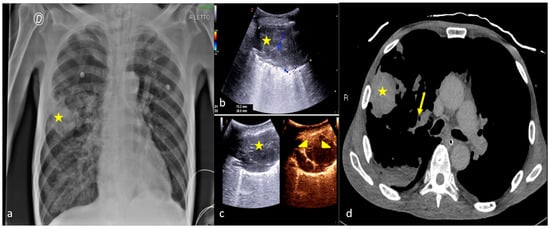

2.4. Cardiogenic Pulmonary Edema

2.5. Acute Respiratory Distress Syndrome

2.6. Pulmonary Contusion